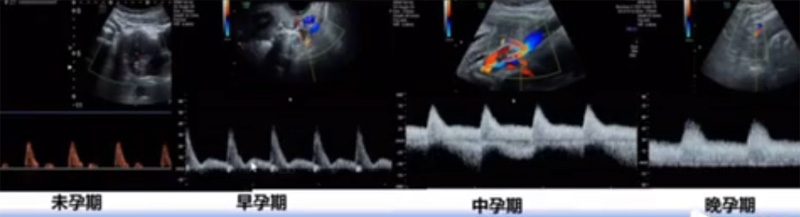

位于輸卵管的后下方,子宮兩側(cè)的后上方;借卵巢系膜與子宮闊韌帶后層相連。正常成人卵巢約4x3x2cm,跟睪丸的數(shù)值差不多,都是性器官,絕經(jīng)后卵巢萎縮變小、變硬。所以絕經(jīng)后婦女很難找到卵巢,主要功能:生殖和內(nèi)分泌功能分泌性激素。女性的第二性征。女性內(nèi)生殖器的血管分布,動(dòng)脈有子宮動(dòng)脈,卵巢動(dòng)脈,陰道動(dòng)脈,陰部內(nèi)動(dòng)脈。靜脈它是與動(dòng)脈伴行。重要了解的是子宮動(dòng)脈,子宮動(dòng)脈是髂內(nèi)動(dòng)脈前干的重要分支,妊娠時(shí)候血流速度會(huì)增加的,為無創(chuàng)性檢查胎盤血管阻力的方法。未孕期頻譜為高阻力低舒張波形;正常妊娠時(shí)血流速度增加,血流阻力下降。